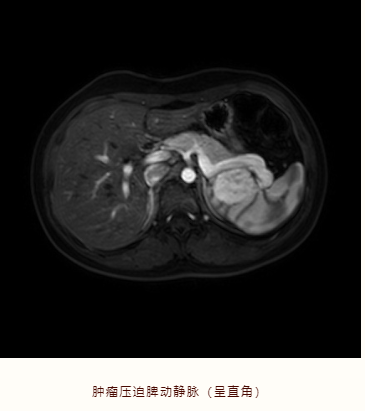

患者18岁,女性,因体检发现脾脏占位性病变2月余就诊于该院肝胆外科,入院后完善相关检查,腹部MRI提示脾脏肿瘤,肿瘤大小约为 4cm×4cm。

术前反复仔细观察患者腹部MRI,仔细清楚分辨肿瘤与脾脏动脉、静脉和肾脏的关系,并通过脾脏动脉流域分析,确定脾脏切除的界面及需要保留的动脉血管支。术中充分游离脾周血管后离段近肿瘤区域的脾蒂,严格按照脾脏动脉血液供应范围,精准地切除肿瘤及靠近肿瘤的部分病变脾脏,保留正常部分脾脏及其供血的主要血管支,顺利完成了腹腔镜下脾脏部分切除。